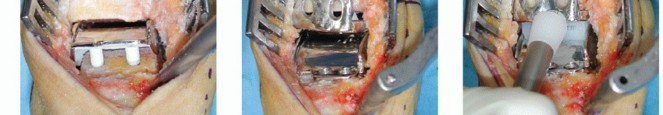

Inserting Trial Implants and Finalizing Cuts

Talar trial

Insert the talar trial using the given impactor. The window on the posterior aspect of the trial allows the surgeon to check its proper fit to the posterior resection surface of the talus (TECH FIG 3A).

If proper position of the talus has been achieved, resect the anterior surface of the talus using a rongeur or the oscillating saw.

Fix the drill guide onto the talar trial (TECH FIG 3B).

TECH FIG 3 • Trial implants. A. First, the trial implant of the talus is inserted, paying attention to obtain a proper fit to the posterior resection surface. B. After resection of anterior surface, the bloc is inserted and the holes for the pegs are drilled. C. The talar trial is removed. The resection surfaces of the talus and tibia are carefully checked for cyst formation. If present, they are meticulously removed. D. The tibial depth gauge is inserted and the size of tibial implant is determined. E. The tibial trial implant is inserted making sure that the tibial component is in close contact with the medial malleolus and the anterior surface of tibia. If necessary, the anterolateral tibia has to be smoothed. Make two drill holes with the provided 4.5-mm drill and remove the trial (TECH FIG 3C).

Tibial trial

Use the tibial depth gauge to determine the size of the tibial implant to be selected; insert it with the appropriate side (right/left) against the tibial surface and hook the posterior edge on the posterior border of the tibia. The size that should be selected can be taken from the scale on the depth gauge (TECH FIG 3D).

Remove the depth gauge and, if necessary, smooth the anterior border of the tibial resection with an oscillating saw or rongeur according to the shape of the indicated resection.

Insert the tibial trial. Try to get the tibial component in close contact with the medial malleolus and the anterior surface of tibia (TECH FIG 3E).

Trial inlay: Insert the 5-mm inlay trial and remove the distractor (Hintermann spreader); if not enough soft tissue tension can be achieved, insert the 6-, 7-, or 9-mm trial.

The use of fluoroscopy is highly recommended to check the position of implants while the foot is held in neutral position, particularly the following:

Appropriate length of the tibial component: Its posterior border should be in line with the posterior aspect of the tibia so that the tibial surface is fully covered.

Proper fit of the tibial component to the tibial surface

Proper fit of the posterior edge of the talar component to the posterior surface of the talus

Point of contact of the talar component to the tibial component. This contact point should be between 40% and 45% of the tibial component when the anterior border is taken as 0% and the posterior border as 100%, respectively. If the point of contact is too posterior, ligament balance will not be achieved.

Insertion of Implants

Insert the final implants previously selected as follows:

Fill the talar component with bone matrix (IsoTis) to get the cysts filled and then insert the talar component so that the pegs can glide into the two drilled holes; use a hammer and impactor to obtain a proper fit of the component to the bone (TECH FIG 4A).

Insert the tibial component along the medial malleolus until proper fit to the anterior border of the tibia is achieved (TECH FIG 4B).

Insert the inlay (same size as the talar component). Remove the distractor (Hintermann spreader). Hammer and impactor might be used for appropriate fit to the bone (TECH FIG 4C).

TECH FIG 4 • Insertion of definitive implants. A. The talar component is impacted first. B. After insertion of the tibial component and the polyethylene insert (C), the tibial component is impacted to obtain a proper fit to the tibial resection surface. D. The foot is moved in dorsiflexion with the surgeon's maximal power, hereby settling of the implant might be improved and remaining soft tissue contracture on the posterior aspect of the ankle might be released. (continued) While the foot is moved in dorsiflexion with the surgeon's maximal power, settling of the implant might be improved and remaining soft tissue contracture on the posterior aspect of the ankle might be released (TECH FIG 4D).

It is furthermore highly recommended to check the position of the implants by fluoroscopy, as described earlier for the trial implants (TECH FIG 4E,F). This allows the surgeon to detect any remaining bony fragments or osteophytes that could be a potential source of pain or motion restriction.

TECH FIG 4 • (continued) E. Final check of the position of the implants using fluoroscopy. On the AP view, the surgeon checks the position of the implants for any misalignment that may cause edge load of the polyethylene insert, overall alignment in the frontal (coronal) plane, distraction of the ankle (gap between the fibula and talus), and medial and lateral gutters for any bone left that may cause bony impingement. F. On the lateral view, the surgeon checks the position of the implants with regard to the bone surfaces (proper fit) and alignment of the implants with regard to contact area (usually, the apex of the talar component should meet the tibial component 3 to 5 mm anterior to its midpoint). 3. ## Wound Closure